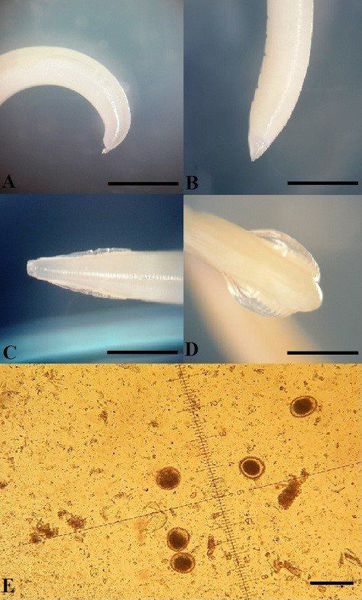

Микрофотографии яиц гельминтов Toxocara canis

Раздел: Фотоэссе